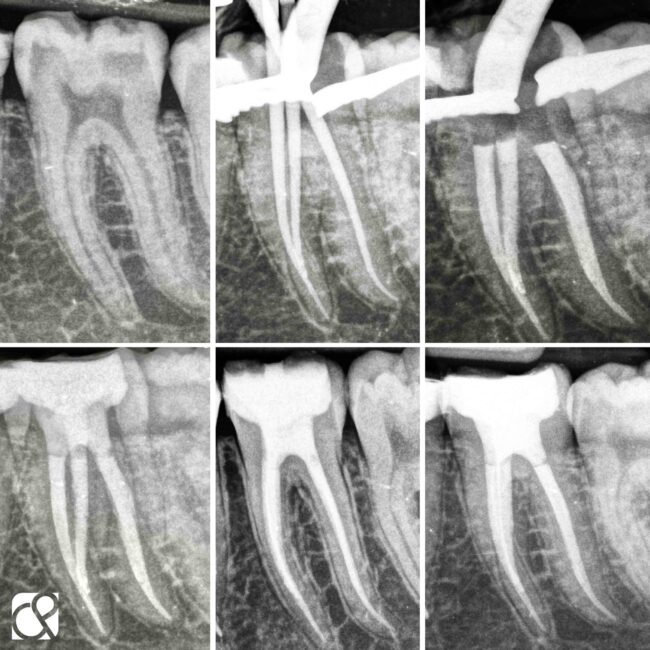

Biopulpectomía en pulpitis irreversible utilizando BlueShaper®, Z-Glider, Fast Pack y Fast Fill

Caso de pulpitis irreversible tratada con los sistemas de instrumentación BlueShaper® y limas Z-Glider ambas de Zarc por el doctor José Conde en su clínica de endodoncia exclusiva, Clínica Conde País.